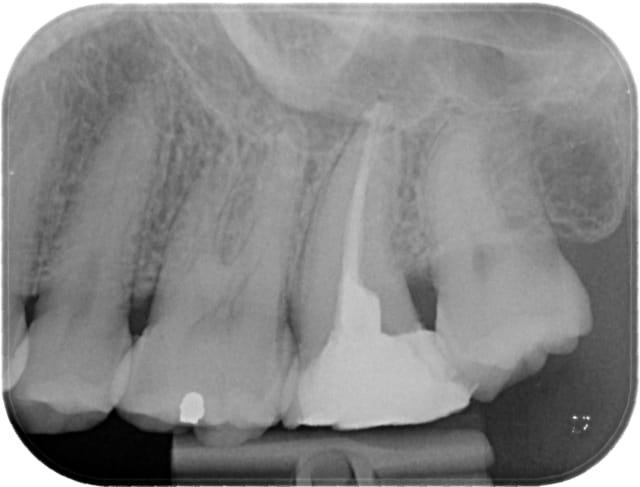

Premier "cas" au wave one... mieux quand j'aurai l'occasion !

Test moi 1962 03 22 x 2011 04 07 19 10 38 3 pkylym - Eugenol

C'est quoi le petit truc au bout du distal ? je vois mal: de la gutta tire bouchonnée ou un fragment d'instrument

Marc Apap écrivait:

-------------------

> C'est quoi le petit truc au bout du distal ? je vois mal: de la gutta tire

> bouchonnée ou un fragment d'instrument

C'est le cone qui s'est plié en deux ! Je l'ai mis une première fois, ça dépassait de deux mm, je l'ai remis une seconde fois, oh tiens c'est bizarre il va bien maintenant ;)